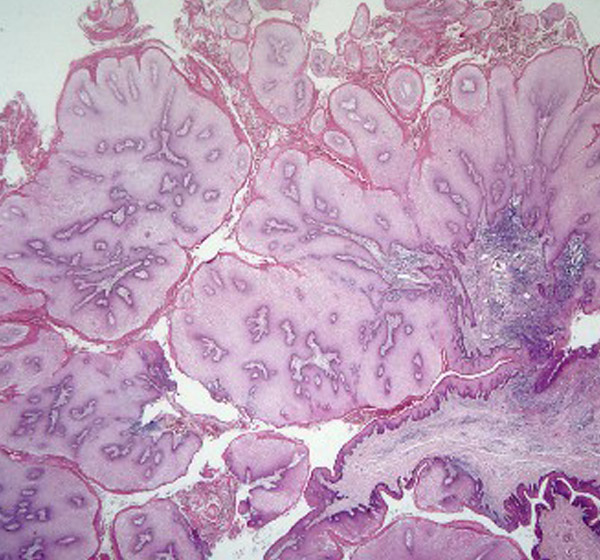

肛门疣鳞状上皮

是人乳头瘤病毒,一种球形dna病毒,能引起人体皮肤黏膜的鳞状上皮增殖

主要侵犯人体的鳞状上皮细胞,引起各类疣状皮肤疾病